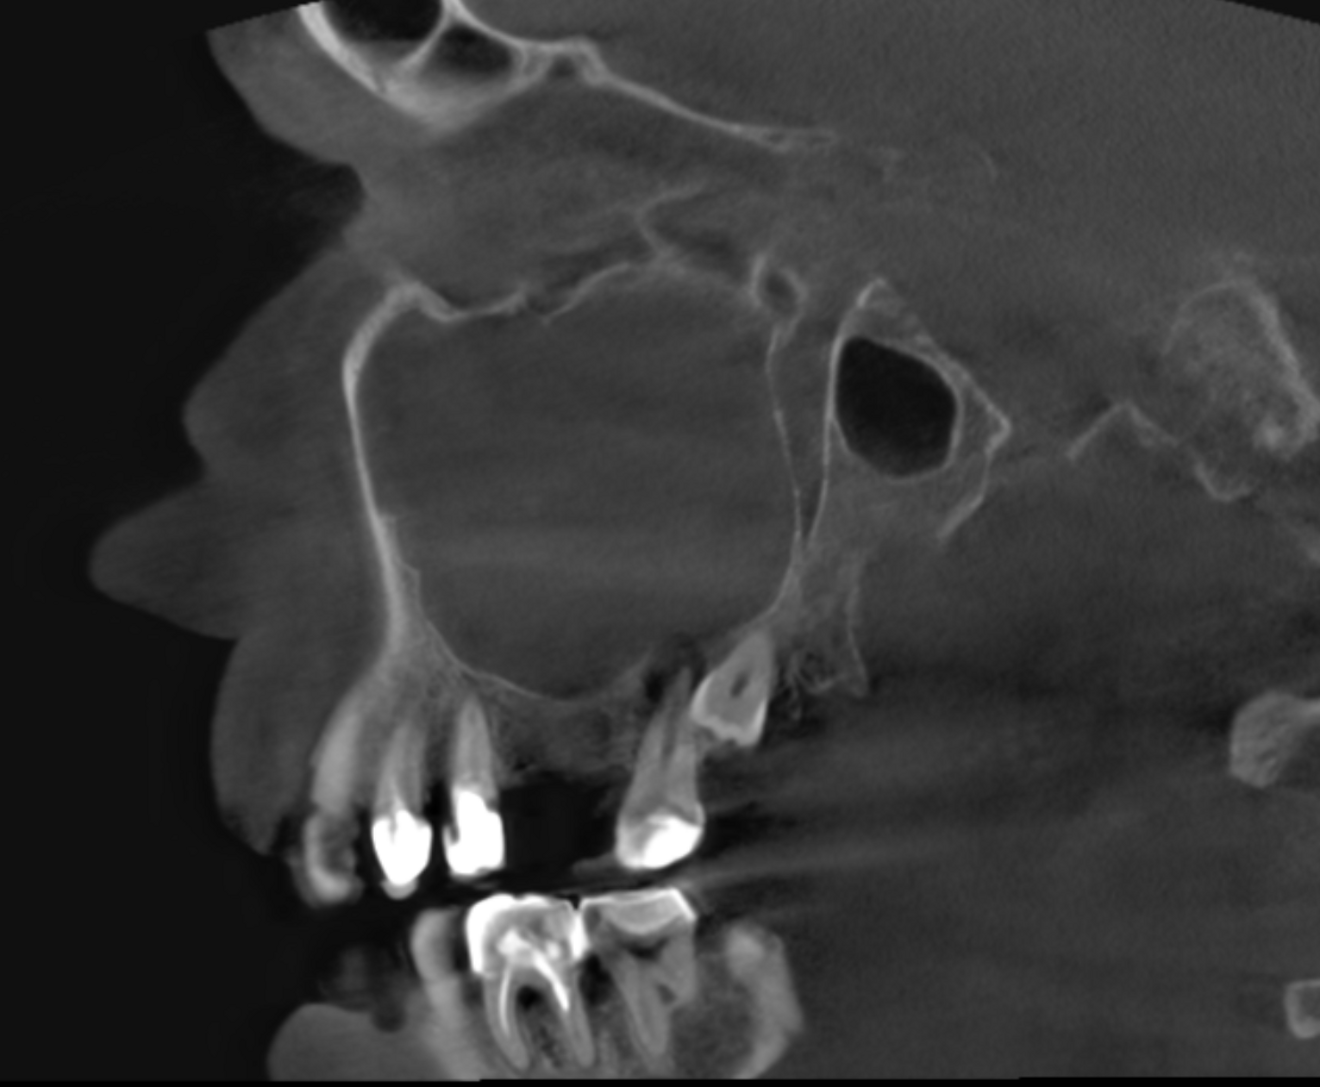

Fig. 2a: Large-volume CBCT scan, sagittal cross-section of the buccal roots.

Fig. 2b: Large-volume CBCT scan, sagittal cross-section of the palatal root.

The extent of the inflammation was shocking (Figs. 2a & b). Not only the maxillary sinus (Fig. 3) but the ethmoid and sphenoid sinuses too were involved, and the inflammation had spread towards the right cavernous sinus as well (Fig. 4). At this point, extraction may have been the first choice for most dental clinicians, but we had to keep in mind that invasive treatment may have increased the risk of cavernous sinus thrombosis, a potentially avoidable possibility. There are very few circumstances under which a dental procedure can cause very severe or even lethal consequences, but this case approached such a situation.

Right after the opening of the pulp chamber, a strong odour emanated from the oral cavity. This was to be expected given that the CBCT scan showed four relatively wide canals and a large pulp chamber in this second molar—features often associated with necrosis and bacterial accumulation. The pulp chamber was rinsed with copious amounts of sodium hypochlorite. Before shaping of the orifices, the tooth was rinsed with saline, followed by a 17% EDTA solution. I prefer to use the Traverse orifice opener (Kerr Dental) to prepare cone-shaped orifices. Its specialised flute design and heat treatment provide reliable flexibility and strength and support debris removal. The working length was then determined in each canal with a #10 K-file and electronic apex locator. The precise determination was essential in this case because the maxillary bone had been damaged by the inflammation around the apices on both the buccal as well as the palatal sides, penetrating into the maxillary sinus.